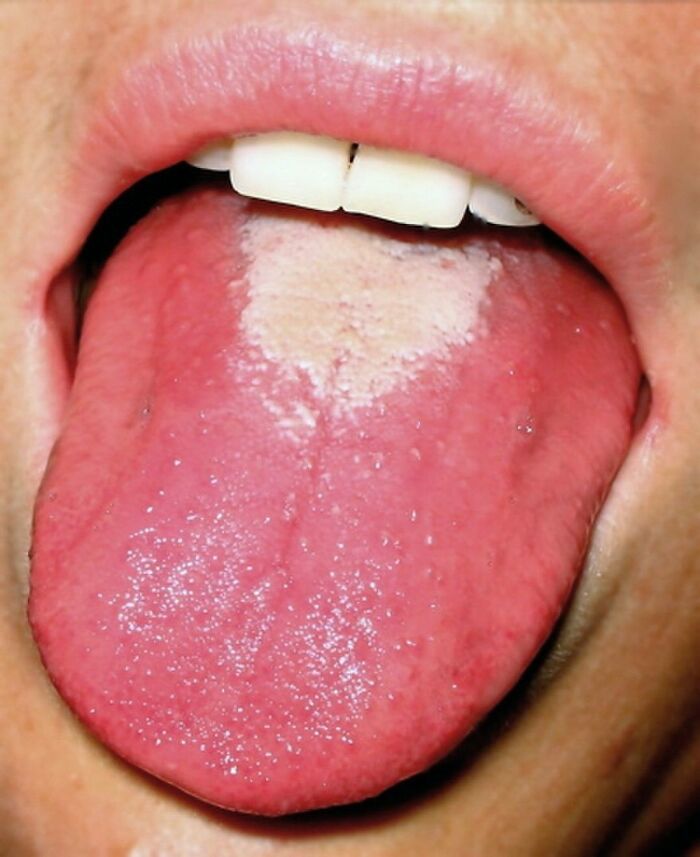

Oral candidiasis, also known as oral thrush, is a condition in which the fungus Candida albicans accumulates on the lining of the mouth.

Strawberry tongue seen in scarlet fever.

Scarlet fever is an infectious disease resulting from a group A streptococcus (group A strep) infection, also known as Streptococcus pyogenes. The signs and symptoms include a sore throat, fever, headaches, swollen lymph nodes, and a characteristic rash. The rash is red and feels like sandpaper and the tongue may be red and bumpy. It most commonly affects children between five and 15 years of age.

Scarlet fever affects a small number of people who have strep throat or streptococcal skin infections. The bacteria are usually spread by people coughing or sneezing. It can also be spread when a person touches an object that has the bacteria on it and then touches their mouth or nose. The characteristic rash is due to the erythrogenic toxin, a substance produced by some types of the bacterium. The diagnosis is typically confirmed by culturing the throat.